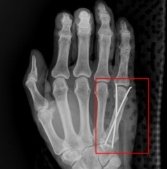

최근 롯데 자이언츠 외야수 황성빈(28)이 이 부상을 입으며 주목을 받았다. 황성빈은 지난 5일 SSG와의 경기에서 1루로 헤드 퍼스트 슬라이딩을 하던 중 왼쪽 네 번째 손가락 중수골에 골절이 발생했고, 정밀검진 결과 플레이트 고정 수술이 필요하다는 진단을 받았다. 이에 따라 그는 최대 10주 동안 경기에서 이탈하게 됐다.

황성빈처럼 야구선수의 경우 슬라이딩이나 타구를 잡는 과정에서 손에 강한 충격이 가해져 중수골 골절이 발생할 수 있다. 이 부상은 일상생활은 물론, 공을 잡고 던지는 야구 동작에 큰 제약을 주기 때문에 철저한 안정과 재활이 필요하다.